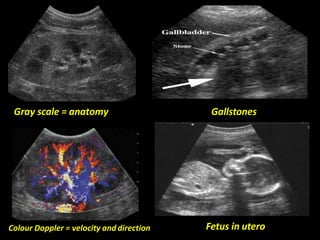

Gray scale = anatomy Gallstones

Fetus in uteroColour Doppler = velocity anddirection

Ultrasonography (ultrasound) •Uses soundwaves of frequencies 2 to 17 MHz. (Audible sound is in the range of 20 Hz to 20 kHz.). •Like SONAR, images result from the propagation of sound waves through the body and their reflection from interfaces within the body. •The time it takes for the sound waves to return to the transducer provides information on the position of the tissue in the body. No ionizing radiation – Uses sound waves to visualize structures • Very operator dependent. • Can not penetrate bone.

Gray scale =anatomy Gallstones Fetus in uteroColour Doppler = velocity anddirection